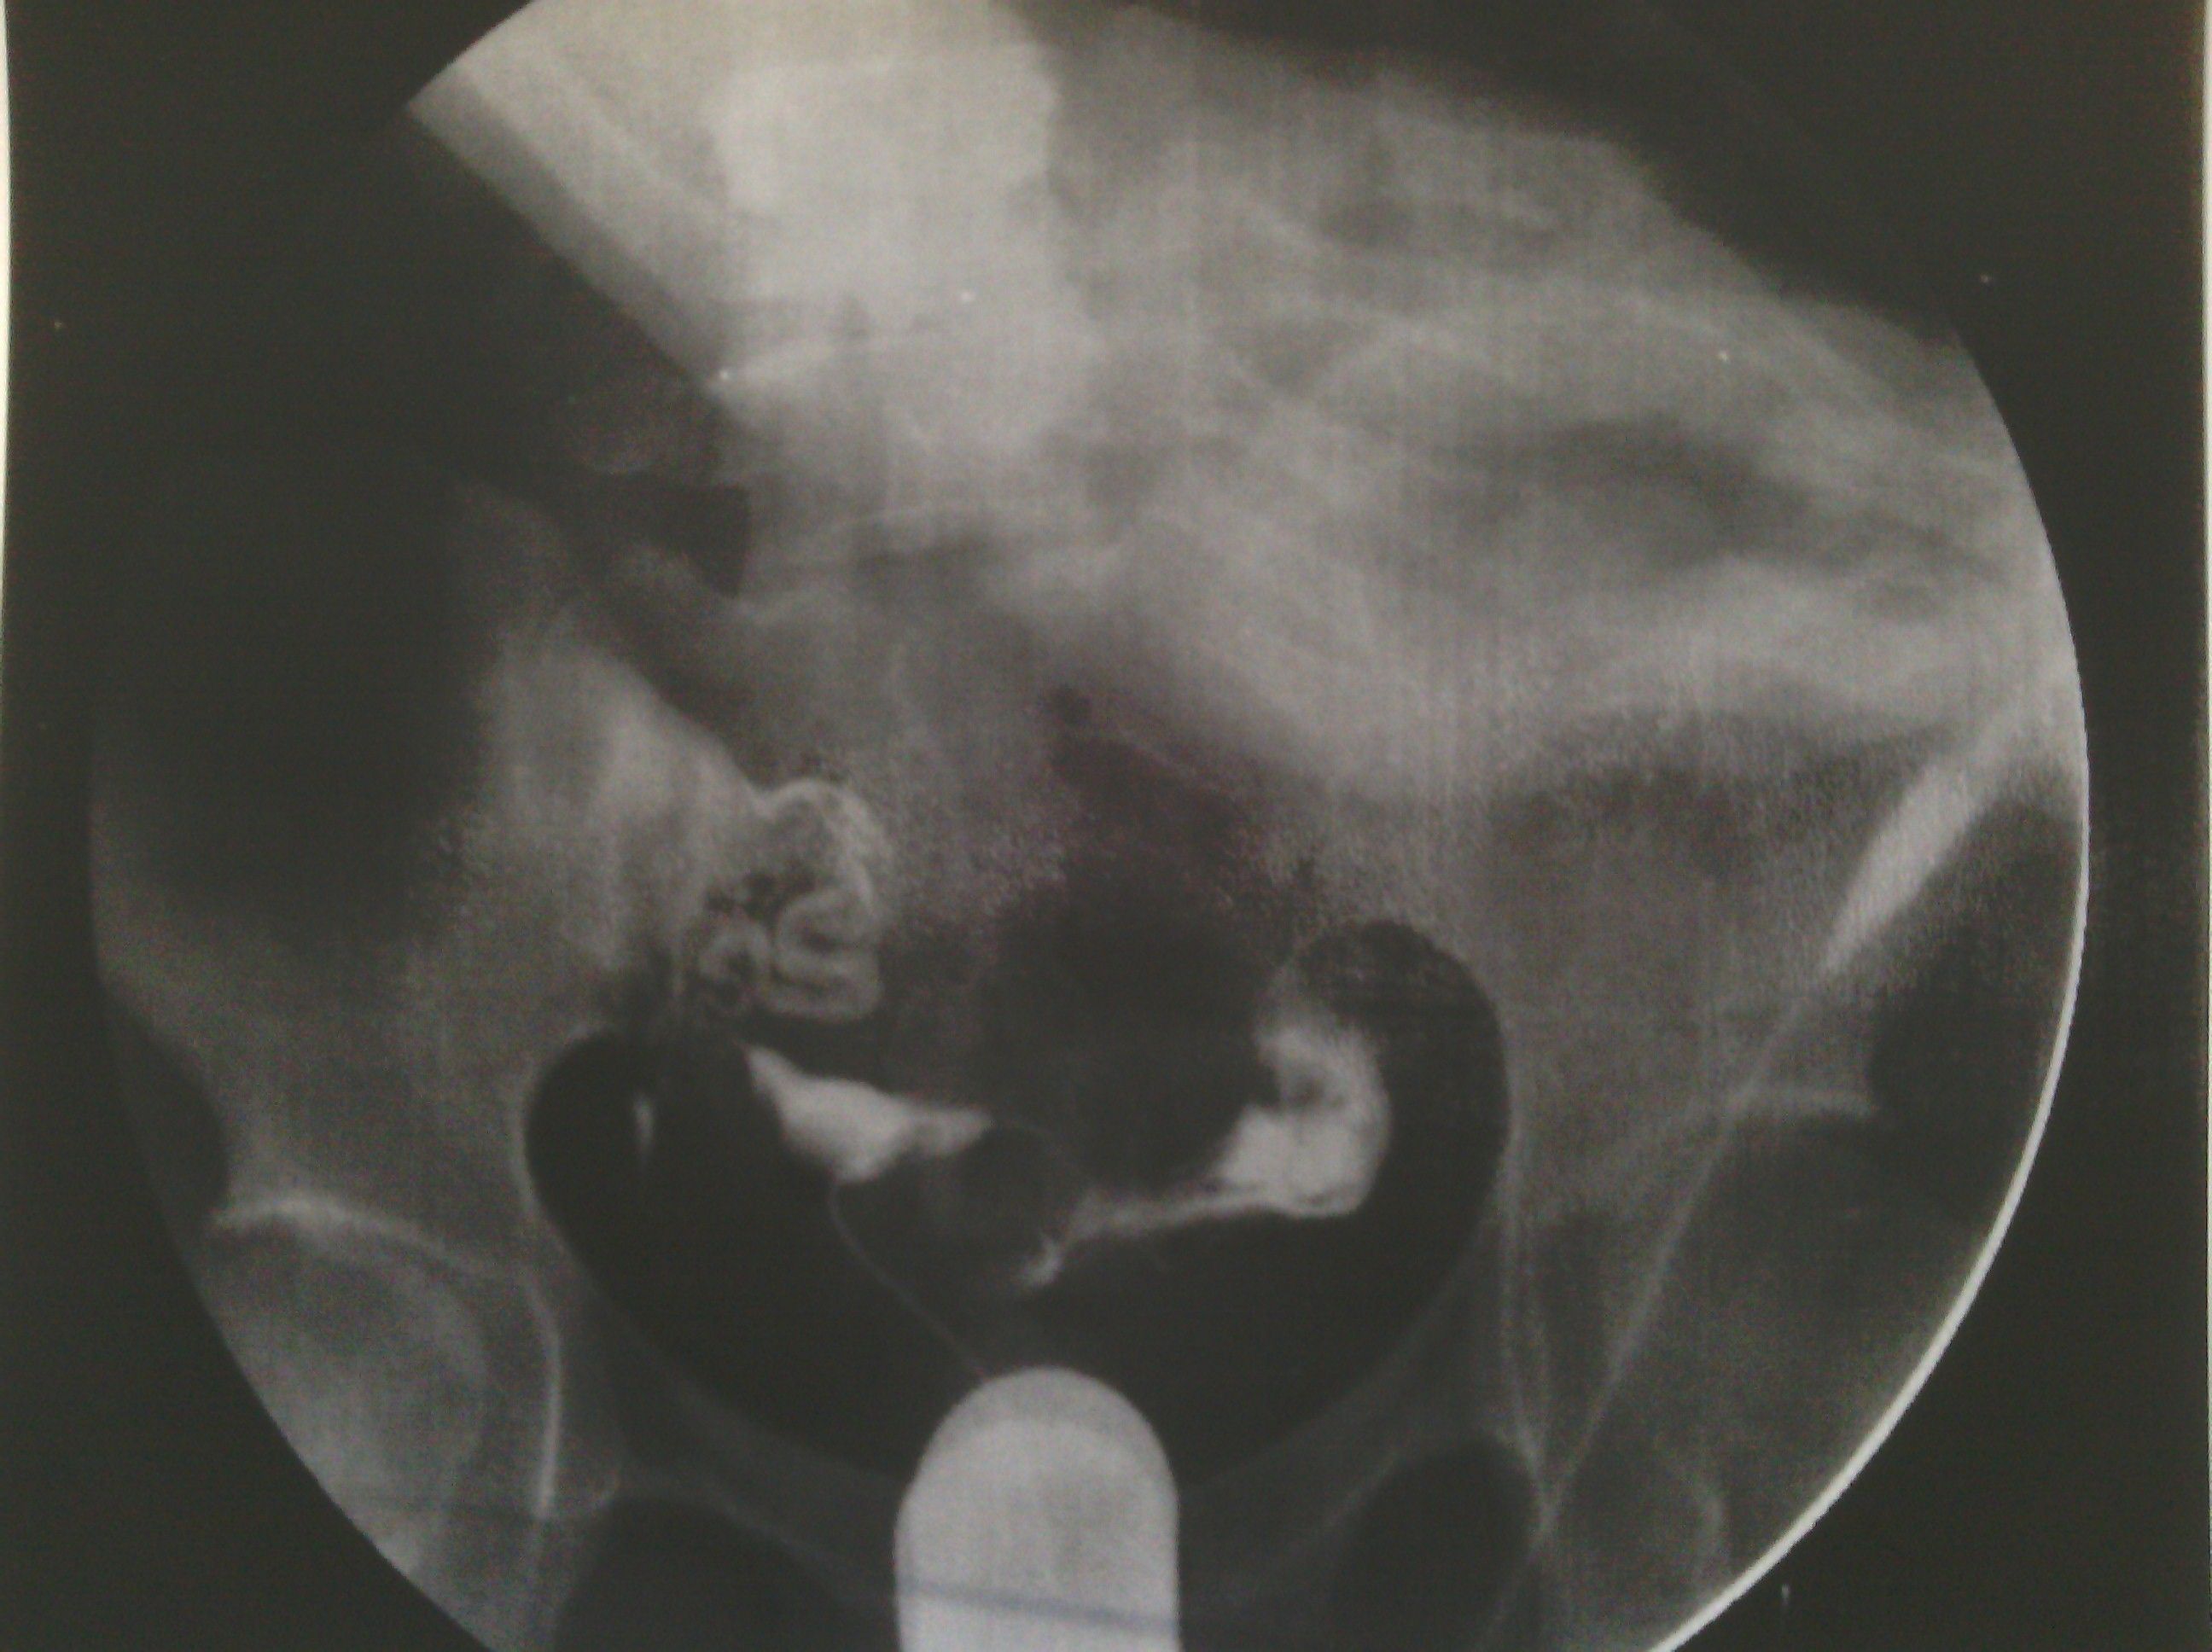

最新输卵管造影图片,麻烦各位大侠帮忙看看,纠结中 各位好,这是我11月6日做的输卵管造影图片,麻烦给看看现在是什么情况。在医院光说通而不畅有粘连,也没说哪个部位粘连,具体的是哪个部位有毛病呢?是间质部,峡部或是壶部。说少量弥散,然而弥散的片子也没延迟拍摄,是造影后直接就出来了,那判断的标准准确吗?看了好几年的病了,慕名到哪个医院去了,都没给过我合理化的建议,都是到哪家,哪家哪个拿手就推荐你做哪个,我现在看见医院两个字就想吐。我就是想,死,我也得死个明白。麻烦各位好心人看看我的片子给我一个合理化建议。现在的输卵管造影是个什么情况应该怎样治疗,在此拜谢各位了。我没啥财富值,对不起各位了。望能看片子解释一二,不胜感激。 点击展开 母婴用户710320885 2013-11-09 08:05 为您推荐: 其他回答 片子没标左右 所以我不清楚是哪边。 可以告诉你的是 面对我左边的输卵管走形上举,有黏连。面对右边的输卵管扭曲扩张。整个状况不是很乐观,具体治疗请咨询妇产科医生。 匿名用户 2013-11-11 14:28 相关问题 求讲解输卵管造影图片 妇科医生专家好:请帮忙看看这份“子宫输卵管造影检查报告”: 帮忙看看造影的报告,双侧输卵管炎不能怀孕了吗?

各位好,这是我11月6日做的输卵管造影图片,麻烦给看看现在是什么情况。在医院光说通而不畅有粘连,也没说哪个部位粘连,具体的是哪个部位有毛病呢?是间质部,峡部或是壶部。说少量弥散,然而弥散的片子也没延迟拍摄,是造影后直接就出来了,那判断的标准准确吗?看了好几年的病了,慕名到哪个医院去了,都没给过我合理化的建议,都是到哪家,哪家哪个拿手就推荐你做哪个,我现在看见医院两个字就想吐。我就是想,死,我也得死个明白。麻烦各位好心人看看我的片子给我一个合理化建议。现在的输卵管造影是个什么情况应该怎样治疗,在此拜谢各位了。我没啥财富值,对不起各位了。望能看片子解释一二,不胜感激。